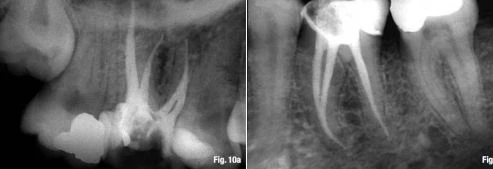

Ngay cả khi chưa có tổn thương quanh chóp. Một vài đồng nghiệp tán thành rằng điểm chóp cuối cùng nằm tại vị trí lỗ chóp sinh lý. Vị trí này bảo tồn nguyên vẹn hình thái chóp răng, và không làm hại đến lỗ chóp chân răng cũng như dây chằng nha chu, vì vậy cho phép lành hương tối ưu (Hình 9a & b). Các đồng nghiệp khác đề nghị rằng điểm chóp cuối cùng nằm tại lỗ chóp giải phẫu, đôi khi nằm ngay chóp răng, hoặc thậm chí ngay chóp răng trên X-quang. Cách làm này chấp nhận khái niệm chóp mở (apical patency) hay kỹ thuật làm sạch chóp (apical clearing technique) (Hình 10a & b).

điểm chóp cuoiió răng trên Xquang

Hình 10. a: Điểm chóp cuối cùng tại chóp răng trên X-quang với kết quả tuyệt vời: hình ảnh kiểm tra trên X-quang sau 2 năm. b: Các ống tủy được trám bít thành công đến chóp giải phẫu.